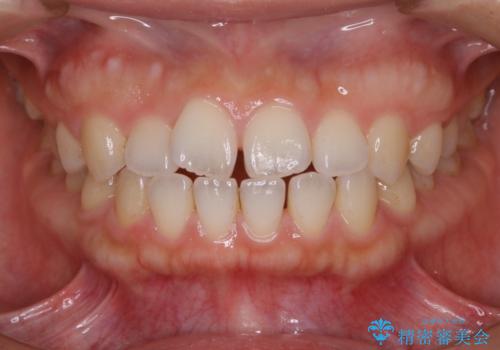

マウスピースで効率的にすきっ歯を治す

- 矯正治療を主訴にご来院されました。

すきっ歯と噛み合わせの治療をしたいとのことで、インビザラインを用いて矯正治療を行うこととなりました。

すきっ歯の場合、ガタつきを治したりするのに必要なスペースが最初から空いているため、そのスペースを利用して比較的短期間で効率よく治療を進めることが可能となります。